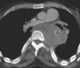

Posterior mediastinal neoplasm

A mediastinal tumor is a tumor in the mediastinum, the cavity that separates the lungs from the rest of the chest. It contains the heart, esophagus, trachea, thymus, and aorta. [Source: Wikipedia ]